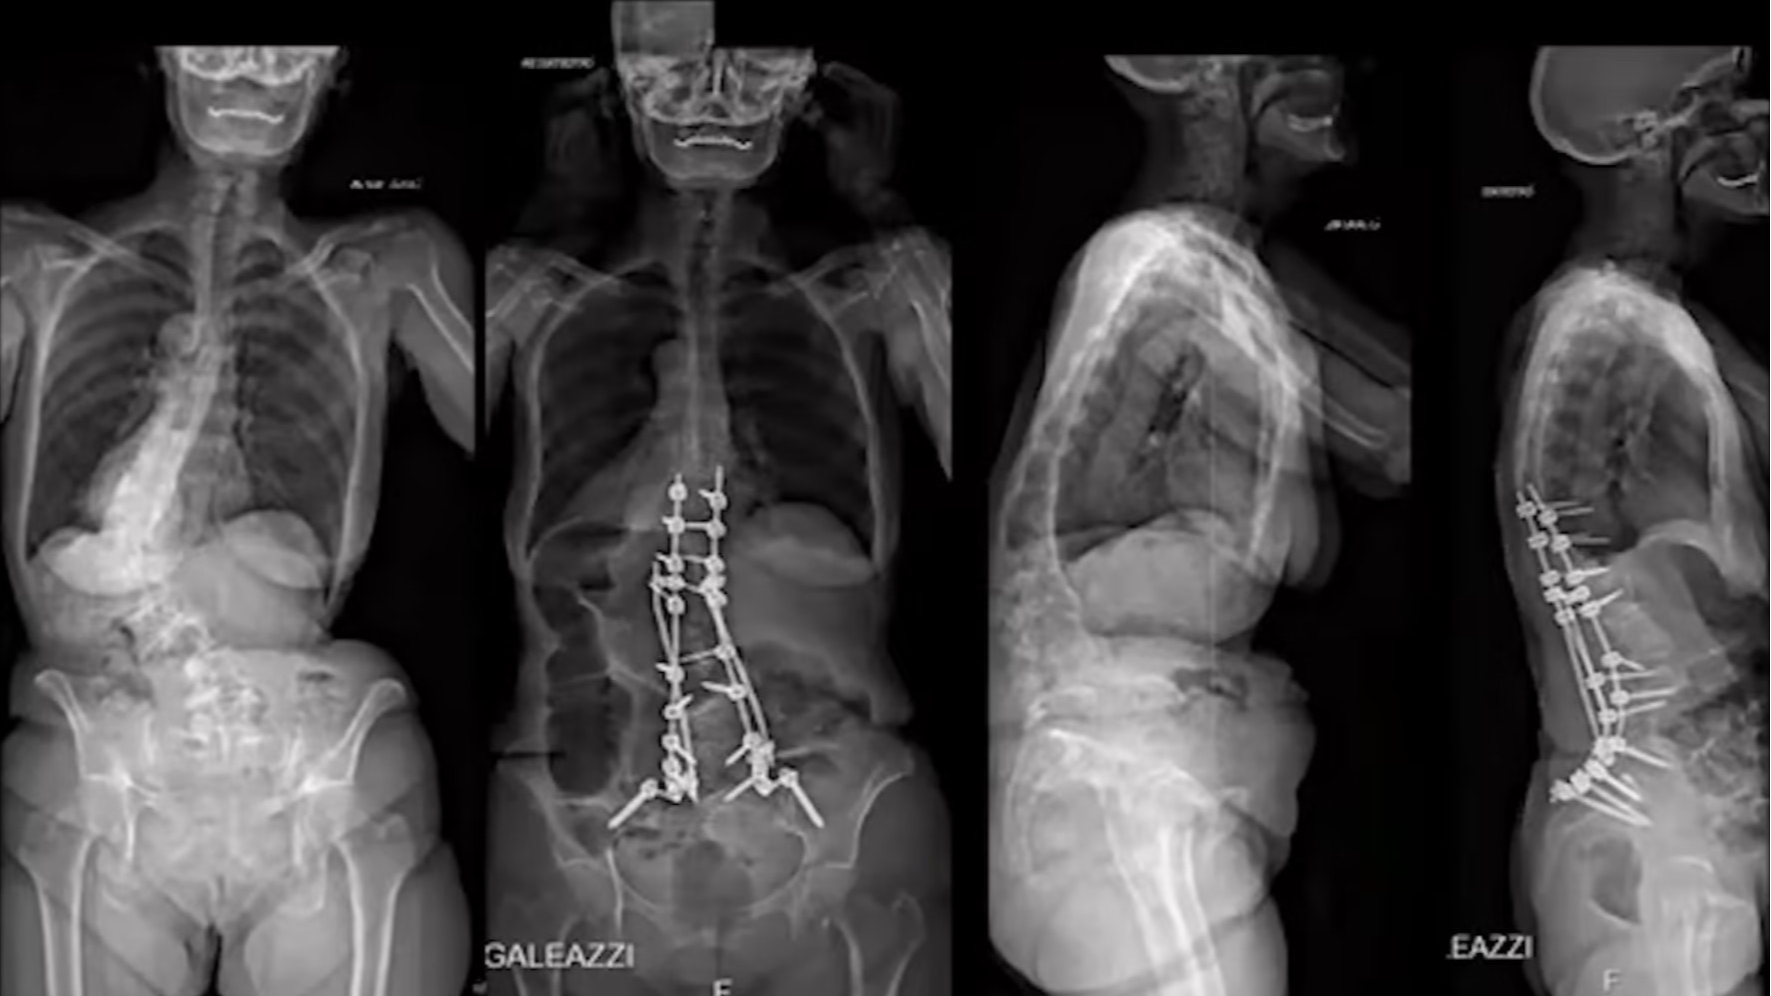

• Osteotomies: Pedicle subtraction osteotomy in the lumbar spine

Osteotomies: Pedicle subtraction osteotomy in the lumbar spine

Lamartina Claudio MD, Professor

GSpine4

IRCCS Ospedale Galeazzi Sant'Ambrogio

Milan, Italy

Project 15-007/12

The technique of this classical lumbar osteotomy is applied in a rigid thoracolumbar kyphosis or kyphoscoliosis and the prac...